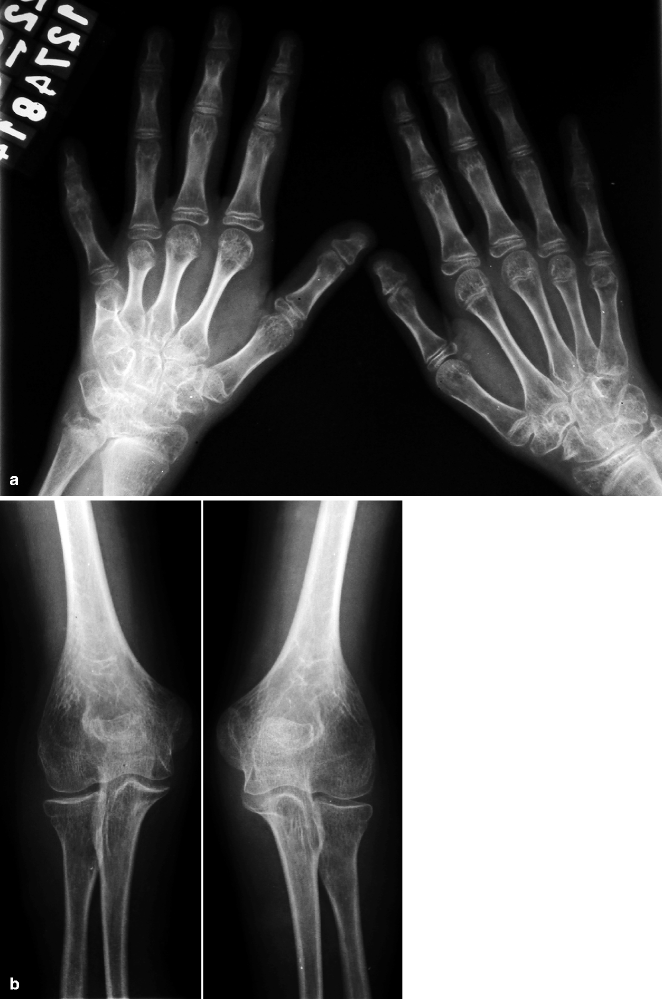

From orthopaedicprinciples.com

Juvenile Idiopathic Arthritis — Juvenile Arthritis Hip Pain Symptoms can vary depending upon the type of jia and can include joint pain, swelling, warmth, stiffness, and loss of motion. To describe the clinical characteristics of hip involvement in juvenile. The evaluation and common causes of hip pain in children are reviewed here. The hip joint is commonly affected in juvenile idiopathic arthritis (jia), especially in cases of systemic. Juvenile Arthritis Hip Pain.